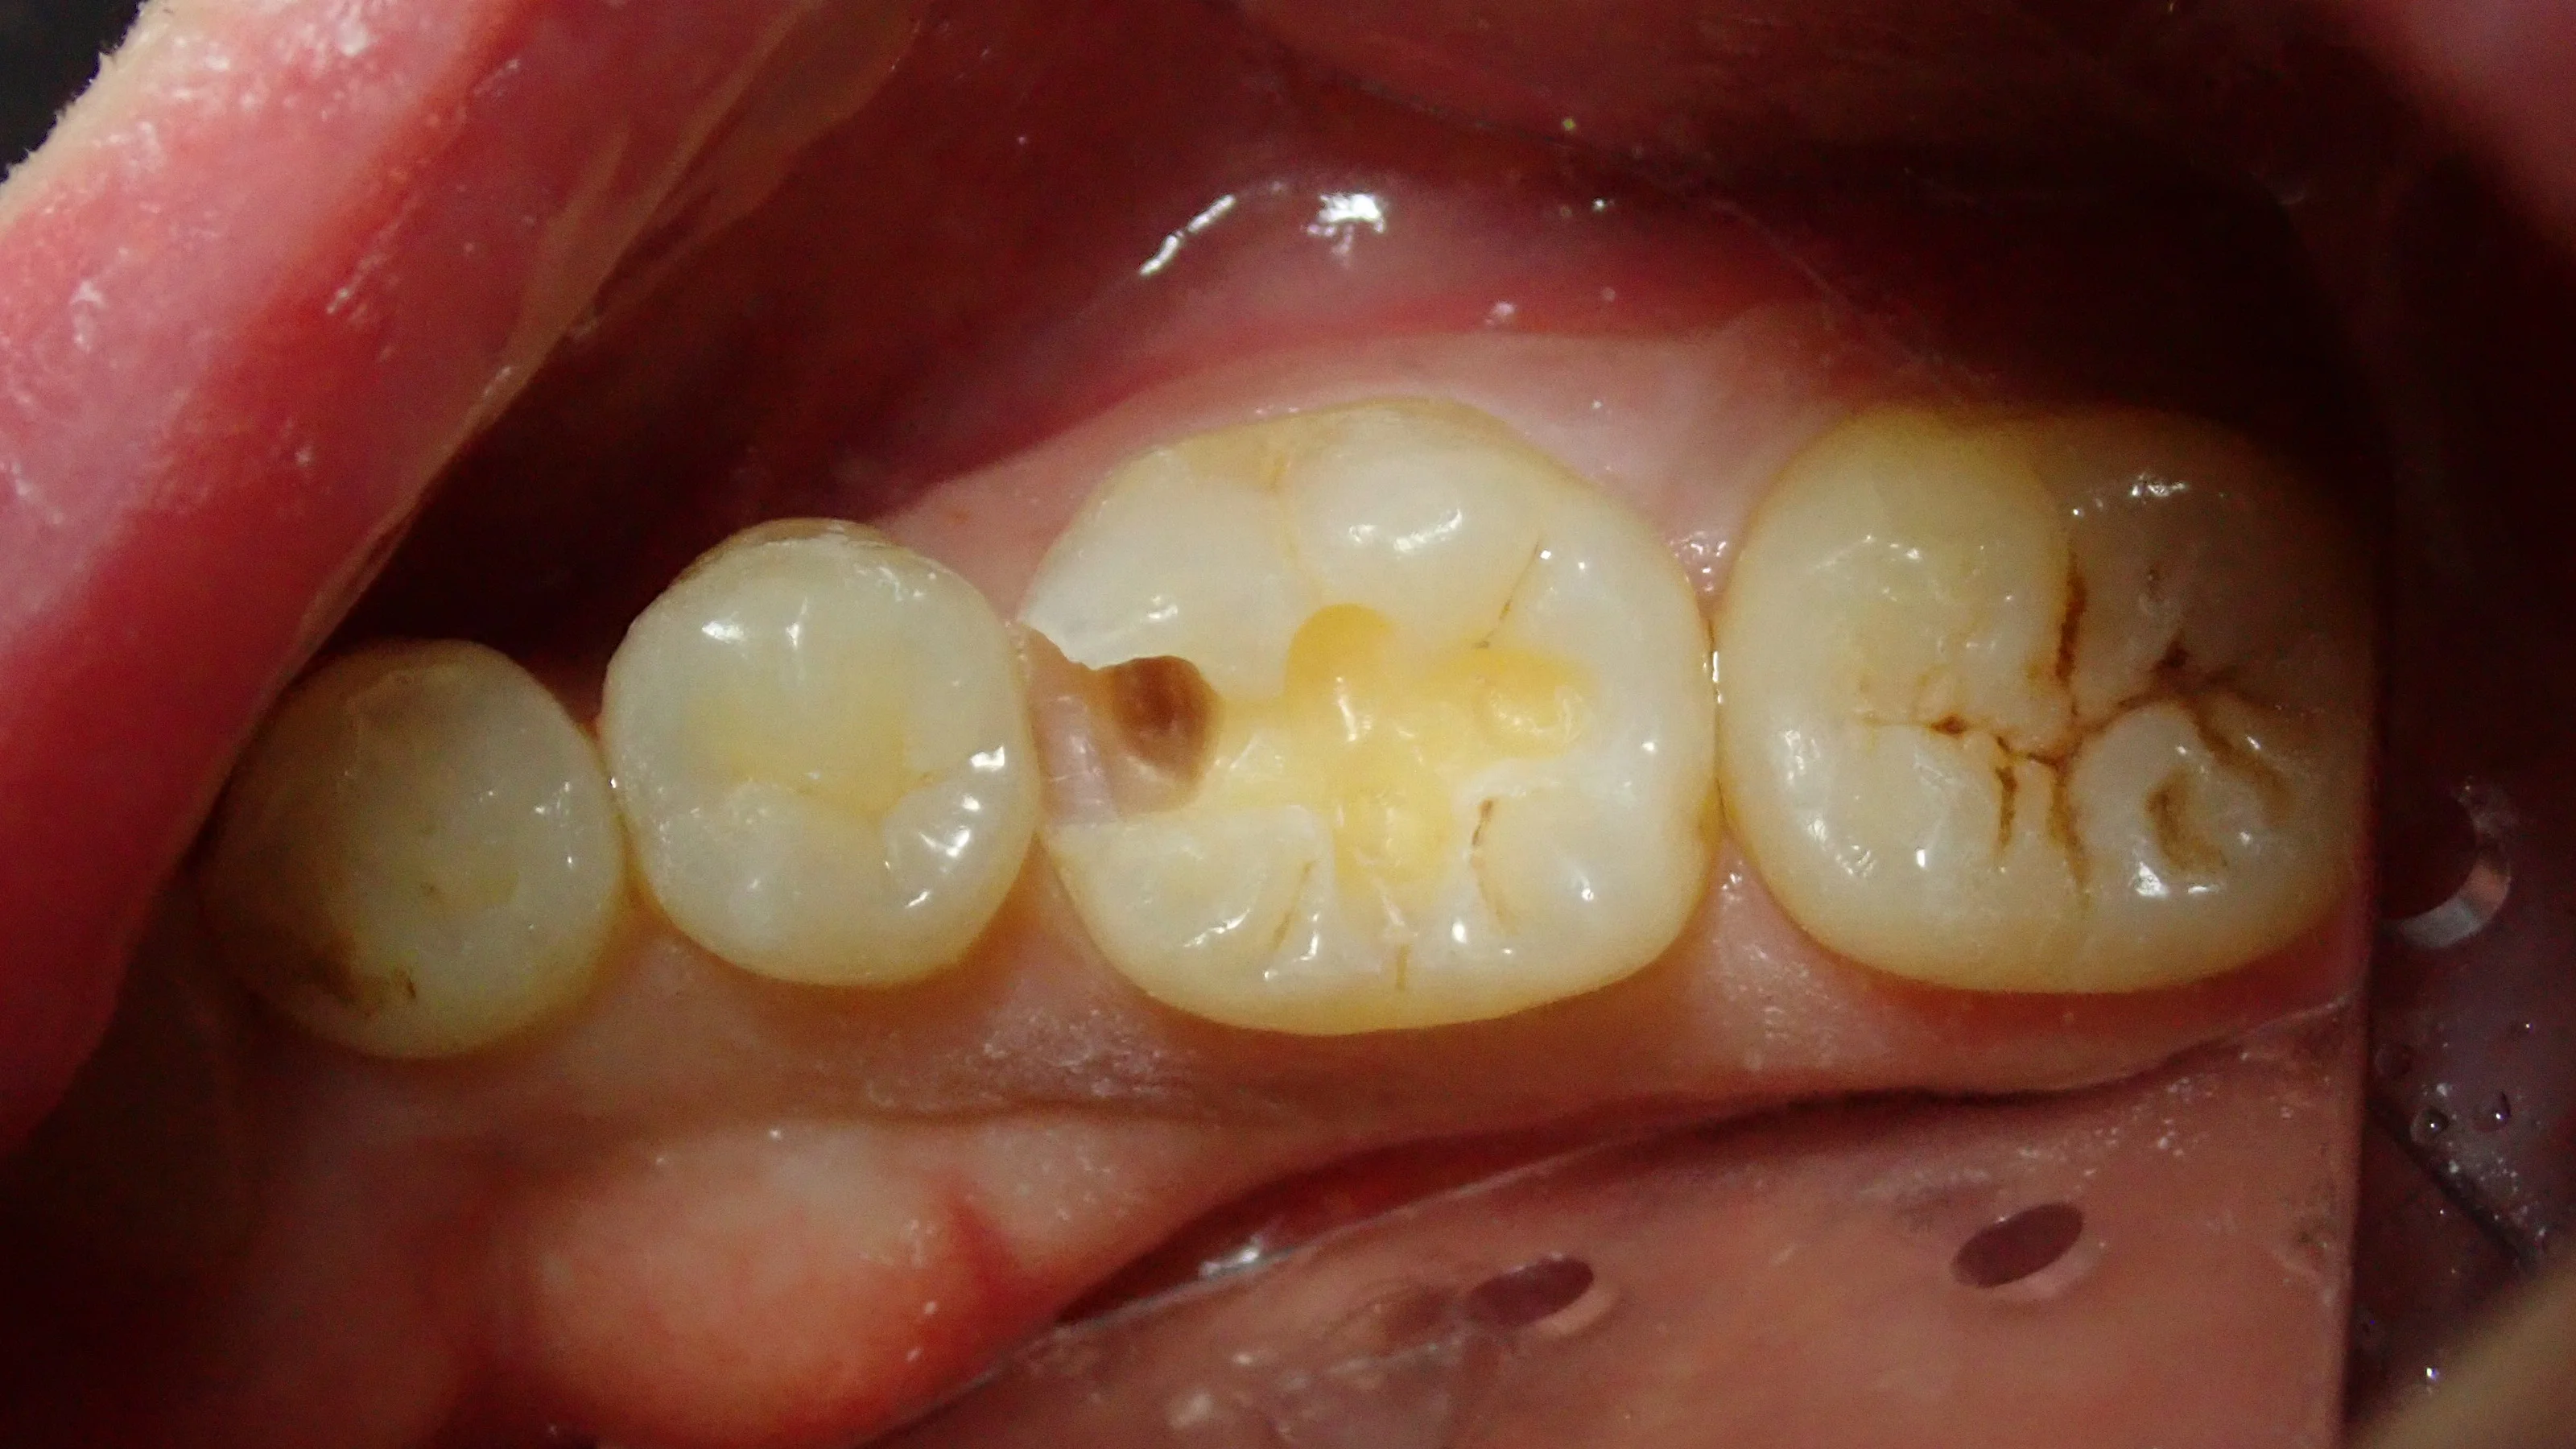

そして、虫歯を取り切った後の写真です。

一部着色が残っていますが、ここは特に虫歯とかではなく、ただ着色しているだけの部分となります。